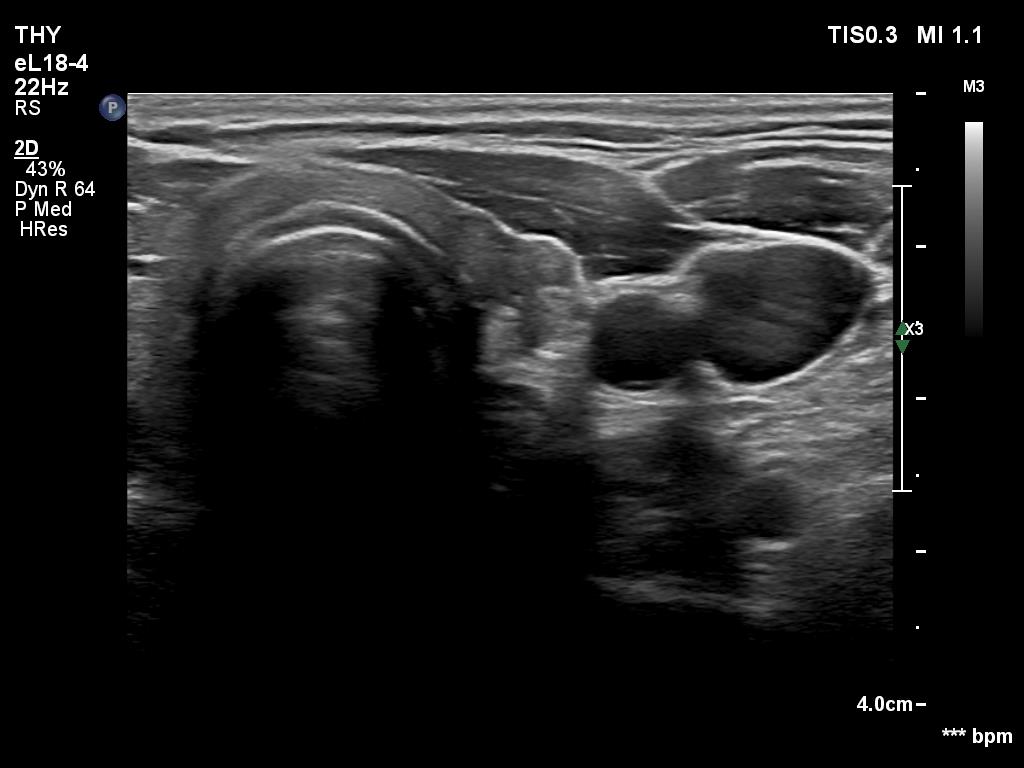

Second examination a year later (second row of images):

Ultrasonography. The thyroid has significantly decreased in size. The echogenicity became normal. The left lobe has already had discrete hypoechoic lesions but the size of them was much smaller compared with the previous visit.

3. if we had any doubts about the diagnosis after the first examination, it disappeared after the second visit: the size of the lobes decreased, the echogenicity became normal and although the discrete lesion has been already present, it also decreased in size.